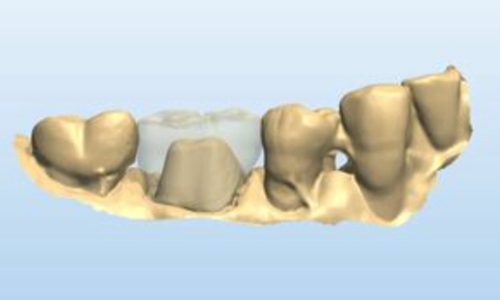

The impression was sent to the laboratory (Peter Kouvaris, New York City) and a lithium disylicate (e.max, Ivoclar Vivadent) crown was prescribed using digital technology. In the lab, Peter scanned the impression and developed the digital information (Fig. 4).

Fig. 4 Fig. 5 Fig. 6

Figure 5 shows a digital image of the teeth in occlusion. Peter designed the crown using digital technology.